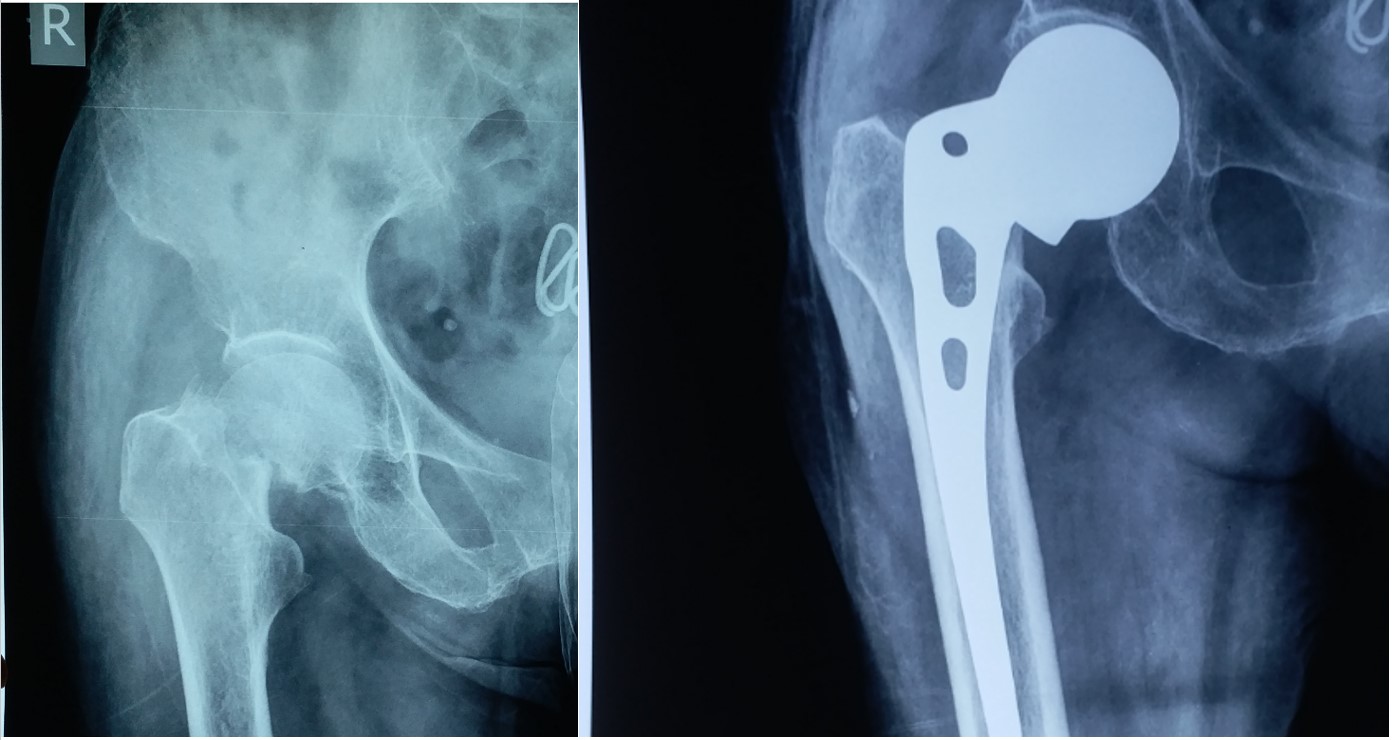

AVN